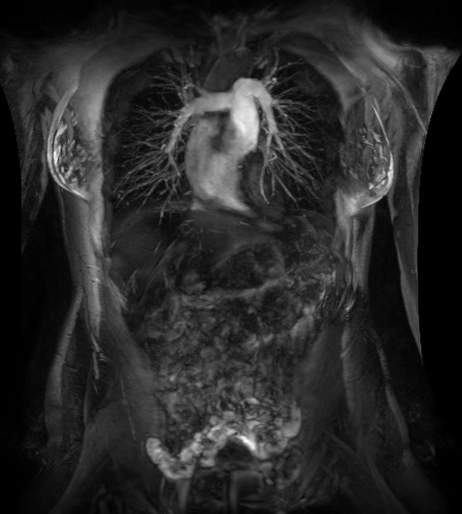

MR,早期肝臟健康(Resoundant)檢查

全面、定量、無輻射、快速(屏氣)和無創(chuàng)的肝臟評估。

定量評估甘油三酯脂肪濃度和R2 *(IDEAL IQ),肝臟組織硬度即時分析(MR Touch)??赡苡兄谠u估非酒精性脂肪性肝?。ㄖ荆?、脂肪性肝炎(炎癥)和肝硬化(纖維化)。致力于讓磁共振成像和活檢一樣精準、有效。(待FDA 510K審批,未上市銷售)